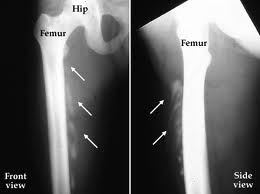

For hundreds of thousands of people, injuring a muscle through an accident like falling off a bike or having surgery can result in a strange and serious complication. Their muscles start growing bones.

The discovery -– in human and animal tissues — offers a molecular target for drugs to potentially prevent and treat the abnormal bone growth, which is called heterotopic ossification.

Lixin Kan, research associate professor at Feinberg and lead author of the paper, found that Substance P is dramatically increased in newly damaged tissue of patients who have the more common heterotopic ossification as well as a rarer and debilitating genetic disease. In the genetic disease, connective tissue begins to ossify and turn into bone. It’s called fibrodysplasia ossificans progressiva (FOP).